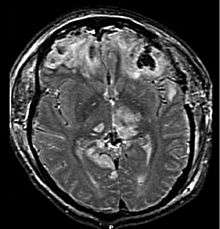

| CT scan showing cerebral contusions, hemorrhage within the hemispheres, subdural hematoma, and skull fractures[1] | |

The preferred radiologic test in the emergency setting is computed tomography (CT): it is quick, accurate, and widely available.[69] Follow-up CT scans may be performed later to determine whether the injury has progressed.[2]

Magnetic resonance imaging (MRI) can show more detail than CT, and can add information about expected outcome in the long term.[15] It is more useful than CT for detecting injury characteristics such as diffuse axonal injury in the longer term.[2] However, MRI is not used in the emergency setting for reasons including its relative inefficacy in detecting bleeds and fractures, its lengthy acquisition of images, the inaccessibility of the patient in the machine, and its incompatibility with metal items used in emergency care.[15] A variant of MRI since 2012 is High definition fiber tracking (HDFT).[70]